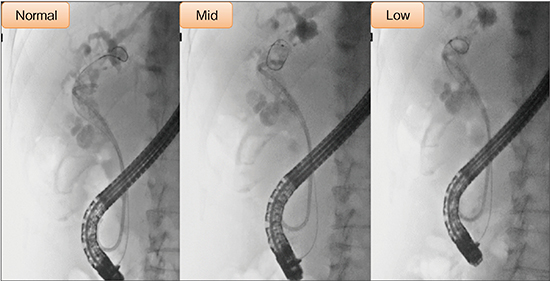

当院では2021年1月にUltimax-iを導入し、現在、4室ある透視室のうち3室にUltimax-i、1室に最新式のオーバーチューブ装置を設置している(図1、2)。Ultimax-iは、Cアームを左右に振ることで、患者の体位変換を行うことなく手技に最適な観察が可能で、他社オーバーチューブに比べて画像のブレも少ない。検査室の大型モニタでは、術中の透視像や内視鏡像、術前の画像などを同時に表示することができる。また、Ultimax-iでは、高画質・低線量検査コンセプト“octave SP”によって、従来より照射線量を約65%低減しても明瞭な透視像が得られる。透視線量モードやパルス透視の切り替えなどによって、さらなる被ばく低減が可能で、当院では通常、パルス透視を7.5fps、透視線量モードをMidにして検査を行うことで、それぞれ91.2%、95.6%の線量低減を図っている(図3)。図4は透視線量モードによる見え方の違いであるが、Ultimax-iでは90%以上の線量低減を行っても、ガイドワイヤが十分確認できる。また、2021年4月の眼の水晶体の等価線量限度の引き下げに伴い、Ultimax-iの被ばく線量測定を行った結果、3名の医師のいずれも被ばく線量限度を大幅に下回っていた。

図3 パルス透視と透視線量モードを活用したさらなる被ばく低減

図4 透視線量モードによるガイドワイヤの見え方の違い

透視線量モードは操作器の液晶タッチパネルにてワンタッチで容易に切り替えられる。